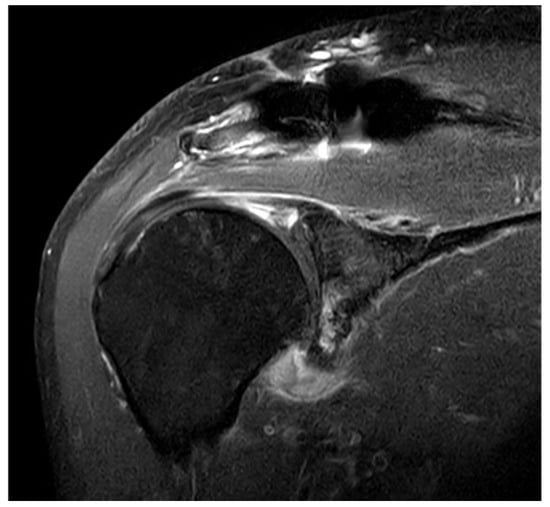

PSE was noted in 17 of 75 (22.4%) patients with DCF and 13 of 84 (15.5%) patients with ACD. There was no difference in the incidence of PSE between patients with DCF and ACD (p = 0.265). Before removing the hook plate, none of the patients with POM or PSS showed iatrogenic rotator cuff lesions on MRI. However, capsular thickening of the axillary pouch with high signal intensity as a typical finding of frozen shoulder was observed in patients with PSS (Figure 1). After removing the plate with or without surgical release for PSS, such as MUA or ACR, there was no recurrence during the follow-up period.

Figure 1. Typical findings on magnetic resonance imaging (MRI) in patients with painful shoulder stiffness. High signal intensity is observed in thickened joint capsule, which is emphasized on axillary capsular pouch.